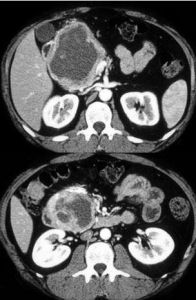

腫瘤的定性檢查

經上述各種檢查已證實有胰島素分泌過多者,應進一步作定位診斷。可採用B型超音波,電子計算機斷層攝影(CT)及選擇性動脈造影等以助診斷。腹腔動脈及腸系膜上動脈,脾動脈造影分別定位胰頭,胰體及胰尾部位的腫瘤。由於多數患者腫瘤體積很小,故B型超聲及CT掃描陰性者不能除外本病。選擇性腹腔動脈造影對細小腫瘤的定位有一定的價值。如有癌腫者還須作肝掃描,如有多發性內分泌腫瘤者,則須查血鈣,磷,尿鈣,尿磷及骨片,以便診斷有否合併甲狀旁腺功能亢進症,必要時行蝶鞍攝片及垂體,腎上腺功能試驗等以助診斷。